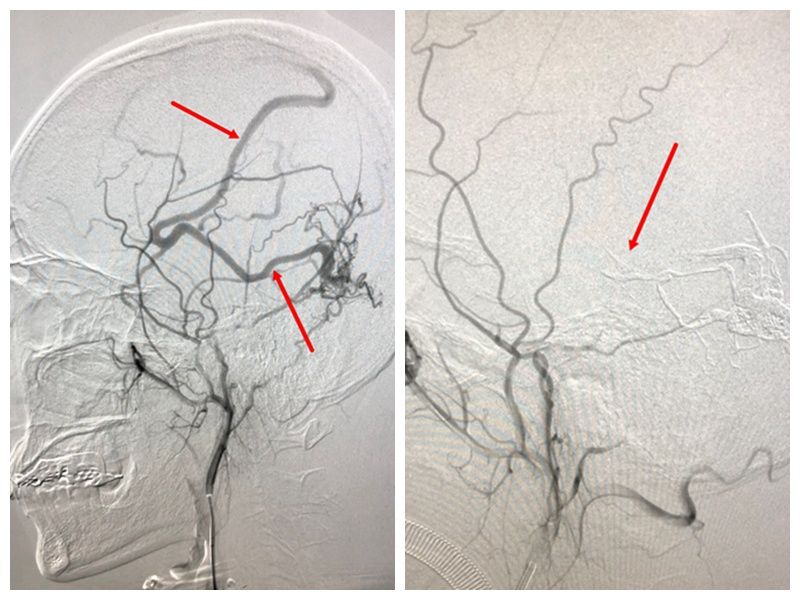

2018-11-16【神经介入】大脑中动脉M2闭塞的取栓治疗

大脑中动脉M1段闭塞行支架取栓治疗最多,效果也最好,而M2段或以远段闭塞治疗较少,主要因为M2段血管迂曲,取栓距离较长,且该段闭塞时往往累及多支M2段所致,取栓的治... -

2018-10-16【神经介入】介入栓塞治疗左颞枕动静脉瘘

患者祖先生,男,51岁,以发作性双眼复视,伴头晕1周之主诉入院,1周前无明显诱因出现视物旋转,复视,以夜间为重,伴有头晕、恶心,未吐,随来我院门诊,做头颅MRI示左... -